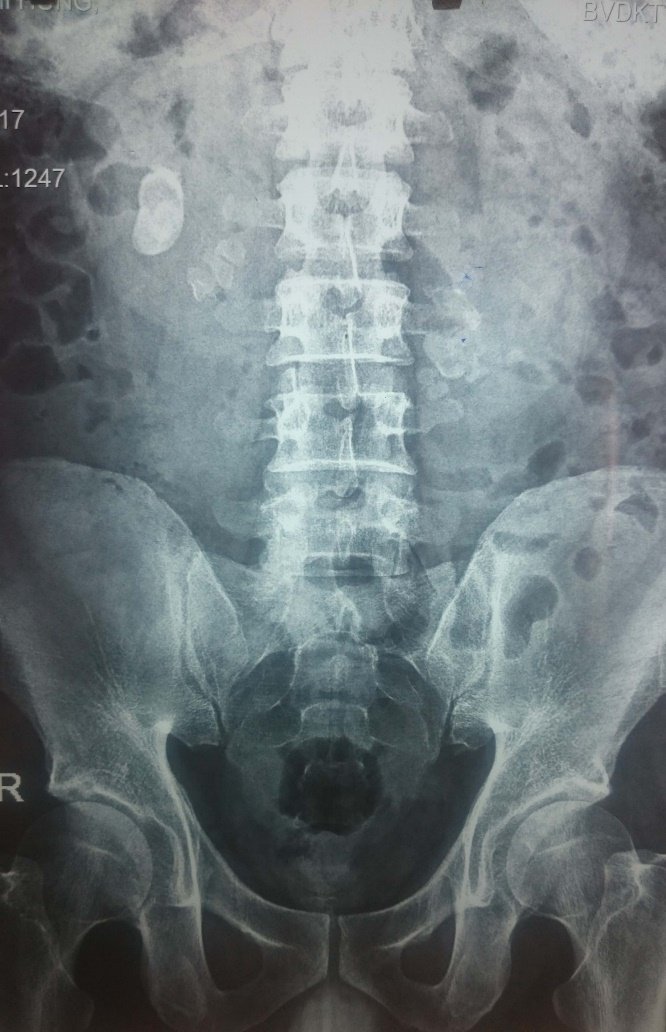

- Chụp X-quang hệ tiết niệu có thể phát hiện sỏi cản quang. Nên áp dụng phương pháp này cho bệnh nhân đã có tiền sử sỏi cản quang; không chỉ định cho bệnh nhân nữ có thai, bệnh nhân ở độ tuổi sinh đẻ cần làm test thai trước khi chụp. Đối với các đối tượng này, tốt nhất là nên làm siêu âm tiết niệu.

- Chụp bụng hệ tiết niệu, siêu âm hệ tiết niệu hoặc chụp CT không cản quang hệ tiết niệu có sỏi niệu quản.